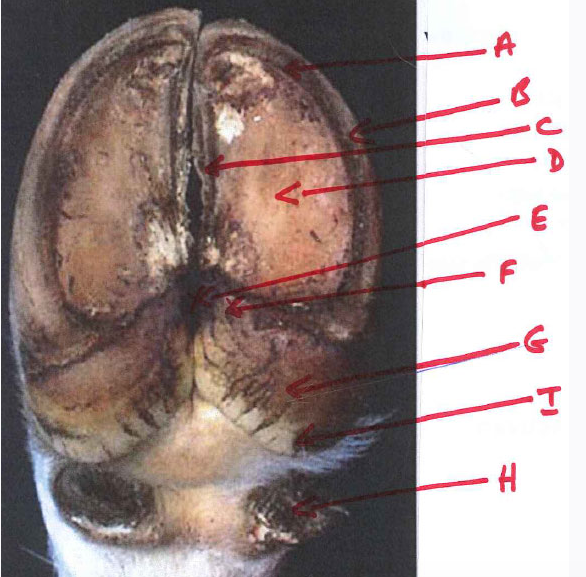

A- white line

B- abaxial wall of hoof

C- axial wall of hoof

D- sole

E- interdigital cleft plantar surface

F- apex of bulb

G- heel

H- dew claws

I- base of bulb

J- interdigital cleft dorsal surface

K- coronary band